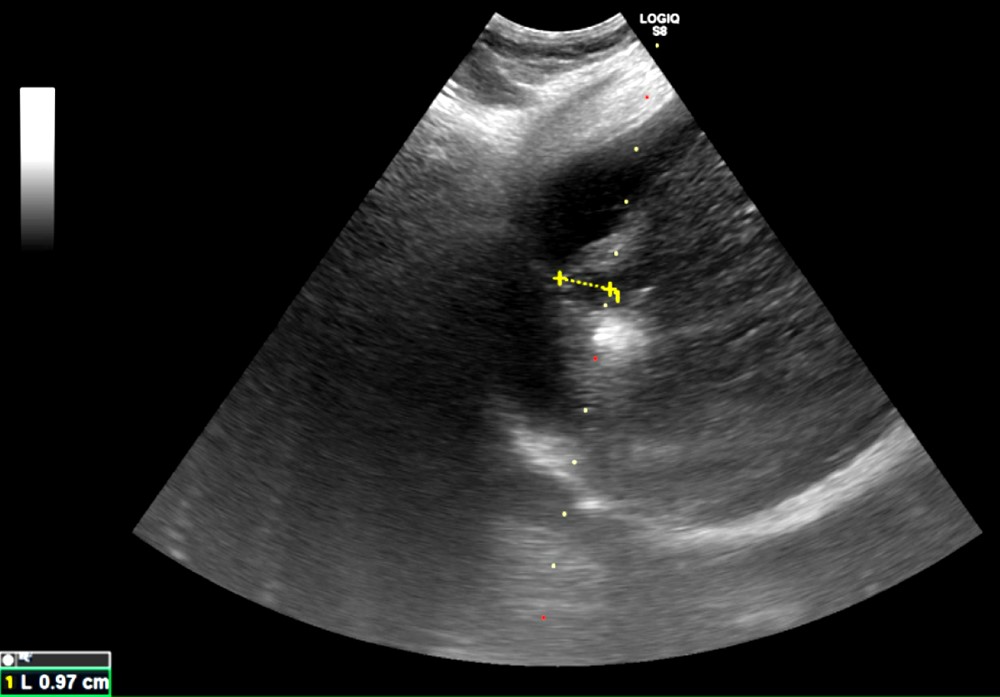

「在第零期使用電燒治療普遍可根治,不需要化療,已經有遠處轉移才會考慮使用免疫療法及標靶治療。」鄭煜明醫師解釋,電燒治療是透過超音波導引定位,使用電極產生電流,造成離子震動產生超過攝氏六十度的熱能氣化腫瘤,比手術更能完整保留健康的肝臟組織。鄭煜明醫師進一步說明,肝癌患者平均五年的復發率高達七成,因此電燒治療對於可能復發、需要多次治療的患者而言更具優勢,且此療法住院時間短,通常三日左右即可出院。適應症方面,電燒治療適用於單顆或三顆以下、每顆腫瘤不超過三公分的病人,且腫瘤位置不能靠近心臟、肺臟等重要器官。治療前需評估凝血功能,若有凝血嚴重異常且無法透過治療矯正者,則不適用電燒治療。

圖為超音波導引下的電燒治療,黃色標記處為肝臟腫瘤,周圍白色處為氣化範圍。圖/台北慈院提供